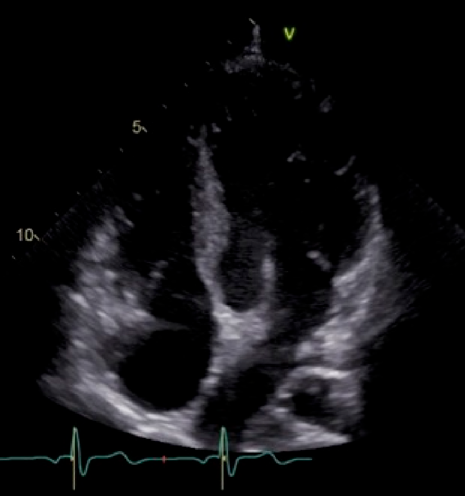

Two years after the operation, the diameter of the TV annulus was found to be 10.8 mm (Z-score: −2.73), and bidirectional flow through ASD was observed on echocardiography. Computed tomography showed that the systemic-to-pulmonary shunt had been occluded, suggesting increased antegrade pulmonary blood flow from the RV. Cardiac catheterization showed a mean PA pressure of 13 mmHg. At the age of 3 years and 6 months, 1.5VR was performed, consisting of the bidirectional Glenn anastomosis, ASD closure, and division of the systemic-to-pulmonary shunt already occluded. The diameter of the TV annulus was measured intraoperatively as 13 mm (Z-score: −2.03). Cardiopulmonary bypass time and cross-clamp time were 174 min and 22 min, respectively. Angiography at 1 year postoperatively showed adequate development of the PAs and unobstructed left ventricular outflow tract (Fig. 2). The SVC and right atrial pressures were 13 mmHg and 6 mmHg, respectively. Thirteen years after the operation, the patient is in a good general condition with normal sinus rhythm. The latest investigation on echocardiography illustrated no sign of right heart failure, such as dilatation of the inferior vena cava, a reversal flow in the inferior vena cava, and right ventricular systolic dysfunction. The TV diameter was 25.3 mm with balanced left and right ventricular cavities (Fig. 3). Table 1 summarizes consecutive changes in the TV diameter, a TV-to-mitral valve diameter ratio, mean PA pressure, and RV end-diastolic pressure. During the course, the patient did not show significant RV diastolic or systolic dysfunction. The TV diameter and RV function did not correlate to each other.

Fig. 2 Left and right ventriculography 1 year after the one and a half ventricular repair

The left ventricular outflow tract has no significant stenosis. The pulmonary arteries are well developed. White arrow indicates the bidirectional Glenn anastomosis.

Fig. 3 A four-chamber view at the latest investigation on echocardiography

Right and left ventricular cavities are balanced in size.